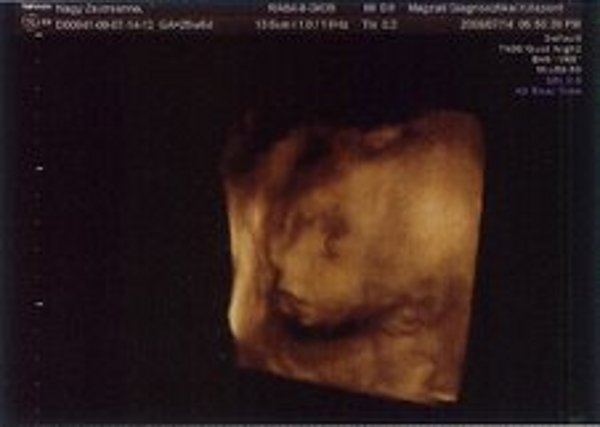

Nézzétek a kukim:

Kép

Zsuzska

Milyen édes kis arcocskája van :)

Édes kis turcsi orra lesz, mint apukájának van.... anyum szerint tiszta apja :lol: :lol: :lol: :lol: :lol: :lol: :lol: :lol:

Leírhatatlan érzés volt látni ilyen formában is. Anyum szerint már most tiszta apja a gyerek :lol: :lol: :lol: :lol: :lol: :lol: :lol: :lol:

Boldog évfordulót kívánok nektek :!: :!: :!: :!: :!: :!: :!: :!:

A doki ott mosolygott végig. De marhára nem tetszett, amikor beszólt nekem, hogy eléggé vaskos a hasfalam :evil: :evil: :evil: :evil: :evil: :evil: Én is majdnem mondtam neki valamit... de hát anyu előtt csak nem :? :? :? :? :? :?